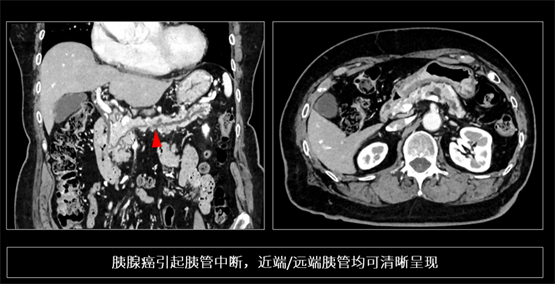

胰腺癌被稱為“癌中之王”,早期病灶往往呈現(xiàn)等密度,且解剖位置深,極易漏診。傳統(tǒng) CT 因軟組織對(duì)比度與分辨率的相互制約,難以捕捉胰管的微小截?cái)嗷蚓窒扌元M窄。依托 PIQE的高空間分辨率與低噪聲特性,INSIGHT Pioneer 能夠捕捉到胰腺實(shí)質(zhì)的細(xì)微紋理改變及胰管的早期形態(tài)學(xué)變化。在一位早期胰腺癌患者的影像(下圖)中,胰管出現(xiàn)細(xì)微中斷,且上下游胰管呈現(xiàn)連續(xù)而清晰的形態(tài),基于這一隱匿性病變的識(shí)別,臨床在進(jìn)一步檢查中將其證實(shí)為早期胰腺癌。這樣的胰管變化,在傳統(tǒng) CT上幾乎不可能這么清楚。